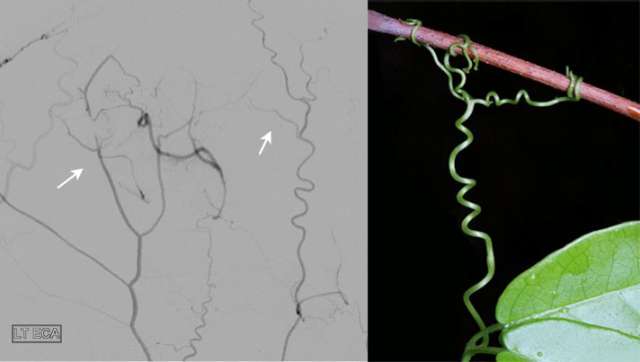

Moyamoya Figure 1

The figure shows the angiogram of a patient with intracranial arterial stenosis. The arrow indicates the narrow segment of the middle cerebral artery.